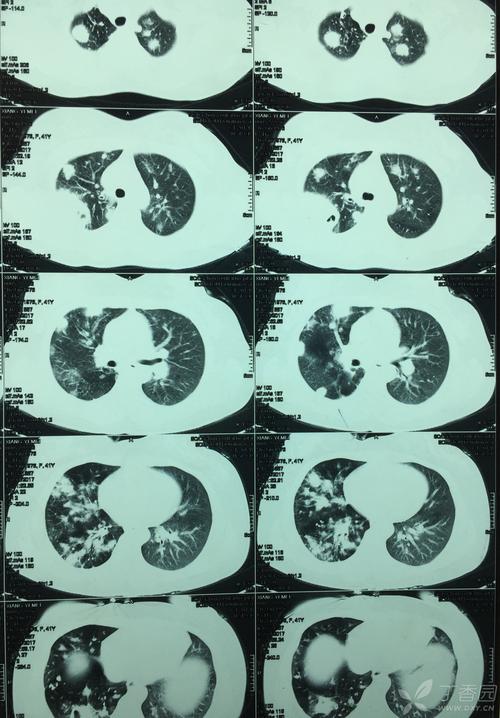

2、患者为中年女性。

4、主要就是因为结核分支杆菌感染,各种病原菌会吞噬大量肺组织,最终导致肺形成一个大的空洞,而且还会在胸腔内形成大量胸腔积液,所以这名女子就是因为这个原因而导致出现这种疾病。